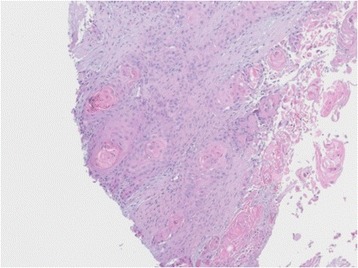

Figure 8.

Microscopic findings of the punch biopsy of the left arm: infiltration by a moderately differentiated squamous cell carcinoma.

A written consent for this case report has been obtained by the patient. The patient is a 52-year-old male Caucasian, residing in the south of Germany. There was no specific family history of malignancy. As far as risk factors are concerned the patient has a smoking history adding up to 45 pack years and still smokes about 10 to 15 cigarettes per day. There was no alcohol consumption reported. He was referred by his dentist to our Department in February 2013 with a suspected OSCC of the floor of the mouth. The conducted head and neck computed tomography (CT) strengthened the clinical suspicion of an OSCC of the right floor of the mouth; a tumor that was also infiltrating the right mandible was demonstrated, along with enlarged lymph nodes at both sides of the neck [Figure 1]. As a part of the staging and planning procedures a laryngoscopy and a pharyngoscopy were performed, as well as biopsies and marking of the boundaries of the tumor with a safety distance. Upon histopathological confirmation of the suspected OSCC diagnosis, the case was discussed during a meeting with our Multidisciplinary Team (MDT), when a primary surgical treatment was recommended. In March 2013 a tumor resection combined with a right mandibulectomy, a neck dissection at level I-V at the right side and level I-III at the left side and a simultaneous reconstruction with a vascular fibular transplant were performed. The histopathological examination of the resected specimen showed a moderately differentiated squamous cell carcinoma with perineural infiltration and one nodal metastasis (pT3 pN1 (1/46) L0 V2 Pn1 G3, local R0) [Figure 2a]. The histology of a macroscopically visible nodule in the neck dissection specimen showed a hemangiosis carcinomatosa (V2) [Figure 2b]. During his stay a heparin-induced thrombocytopenia (HIT) was diagnosed. After a consultation with our Department of Transfusion Medicine the thromboprophylaxis regime was switched from Enoxaparin 20 mg s.c. 1-0-0 to Danaparoid 750 IE s.c. 1-0-1. The postoperative MDT recommended radiation therapy. A locoregional radiation was performed from April 2013 to June 2013 (intensity modulated radiation therapy (IMRT) with a daily fraction of 2,1/1,8 GyHD 65,1/55,8 Gy). After radiation the patient joined our six-weekly tumor-follow-up at our department. Seven months later the decision for the removal of the osteosynthesis plate (Stryker GmbH & Co.KG, Duisburg, Germany, 2.7 mm) of the lower jaw was made and a panoramic radiograph as well as a CT were performed [Figure 3]. It showed no signs for a relapse of the OSCC but pseudarthrosis at two sides of the reconstructed mandible. The pseudarthrosis was treated with a bone graft from the iliac crest. During the surgical procedure several soft tissue biopsies from the right floor of the mouth were taken. No relapse was found within the obtained material. Five months later the decision for the removal of the miniplates (Stryker GmbH & Co.KG, Duisburg, Germany, 2.0 mm), used for the fixation of the iliac crest bone graft, was made. In March 2014 the patient showed up for surgery [Figure 4]. During the clinical examination the patient reported that he has detected a growing mass at his left upper arm about four weeks ago. Clinically the tumor was miming an abscess with redness, heat, swelling and moderate pain. The upper arm was x-rayed and a swelling of the soft-tissue in projection to the lower margin of the deltoid muscle was found [Figure 5]. Sonographically a differentiation between abscess and soft-tissue tumor could not be done [Figure 6]. Therefore MR-Imaging was performed. The MRI described an inhomogeneous tumor at the proximal upper arm with circular extent around the humerus up to the axilla [Figure 7]. Local arrosions of the corticalis suggested malignancy; however, a differentiation between a soft-tissue tumor and a metastatic tumor spread was not possible. Therefore a biopsy was taken and the histological examination revealed a widely necrotic moderately differentiated keratinizing squamous cell carcinoma (G2) [Figure 8]. The case was discussed in an Interdisciplinary MDT. Due to the tumor localization - wrapping the humerus and in close proximity to the brachial plexus and the vascular bundle - the decision to manage it with radiation was made. The patient decided to start radiation therapy at his local hospital. When he showed up for therapy a picture was taken. Noticeable was the rapid progress of the metastasis after the biopsy was taken with a clear infiltration of the skin. Experimental and clinical studies have shown rapid local growth after traumatic interventions, possibly explaining the progress [Figure 9] [4-9].